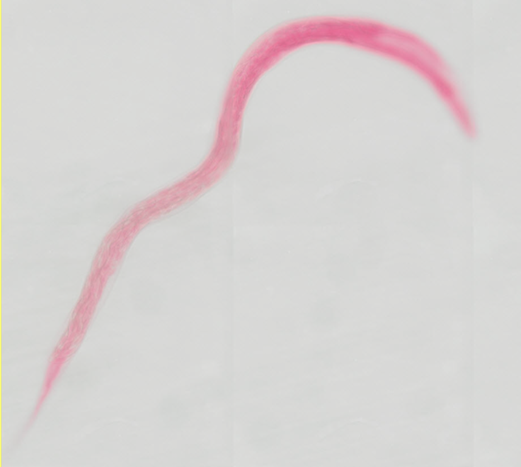

Loa loa - /// - Mikrofilarie